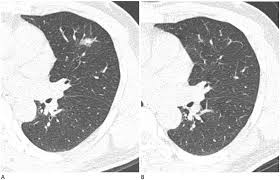

폐결절(pulmonary nodule)은 폐 안에 지름 3cm 이하의 작은 덩어리나 불투명 부위로, 흉부 X‑선이나 CT 검사에서 우연히 발견되는 경우가 많습니다. 대부분은 무증상이며, 양성인 경우가 많지만 일부는 악성(암)일 수 있어 주기적인 관찰이 필요합니다.

- 흉부 X‑선 또는 흉부 CT로 발견

- 결절 크기·형태·경계·석회화 여부 등 특징 분석